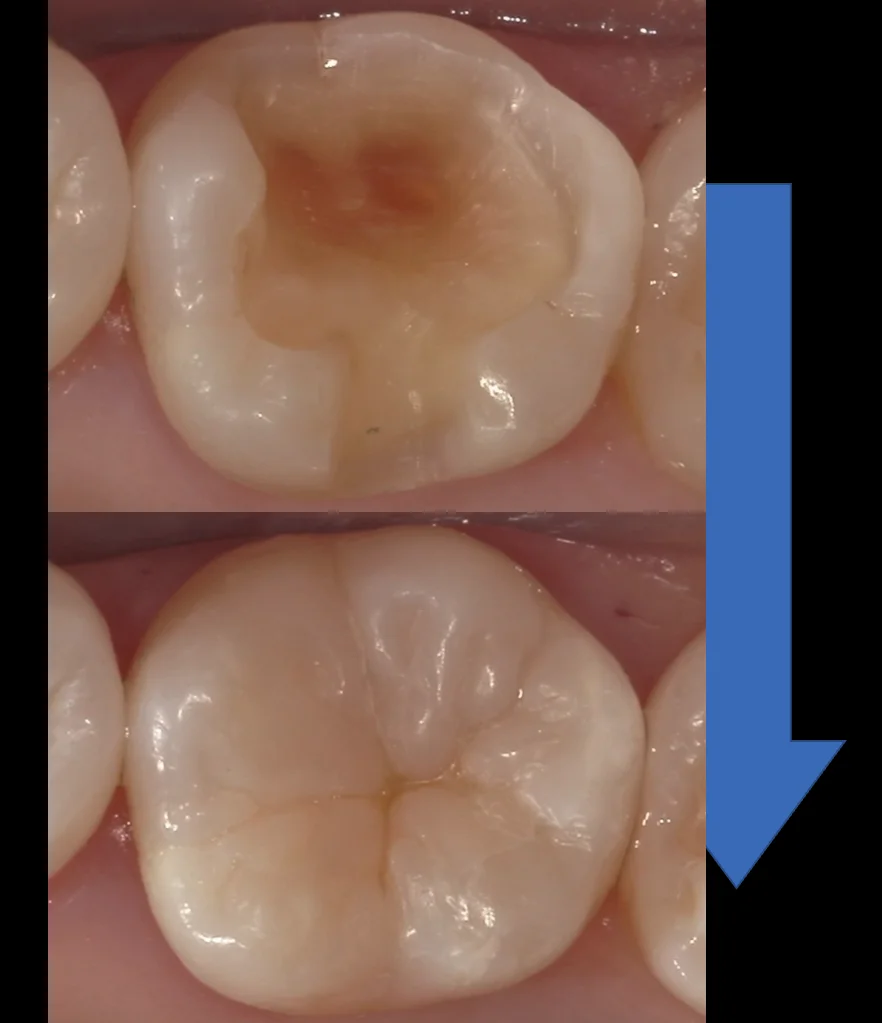

むし歯の必要性を確認して最小限に治療|ダイレクトボンディング症例(右上6・20代男性)

他院で「むし歯がある」と言われたものの、本当に治療が必要か確認したいとのことで来院された20代男性の症例です。確認すると右上6は、噛む面の細いヒビの部分から内部にむし歯が入り込んでいました。一方、手前の歯との間に近い部分は不必要に広げず、残…